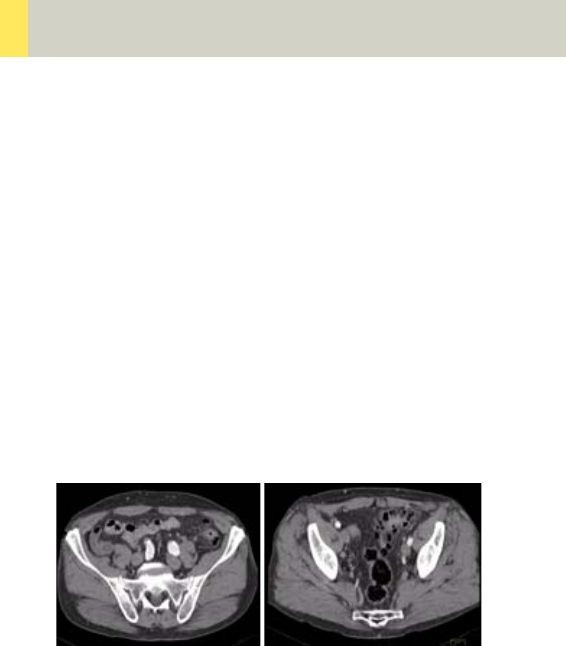

Pelvis 314

•Overview 314

- General Hints 316

- Body Kernels 317

•Scan Protocols 318

- Pelvis 318

- PelvisVol 322

- Hip 324

- HipVol 328

- SI_Joints 330